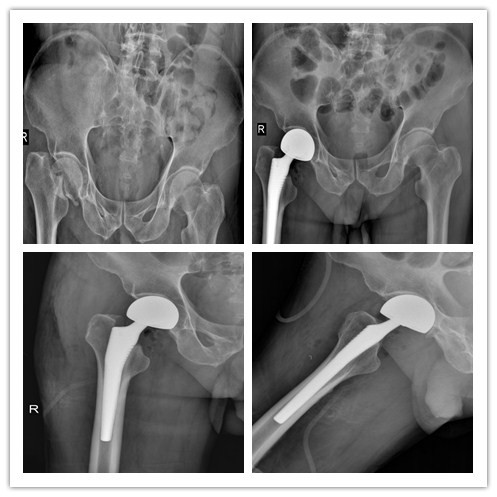

附部分骨折患者术前、术后照片

半髋置换